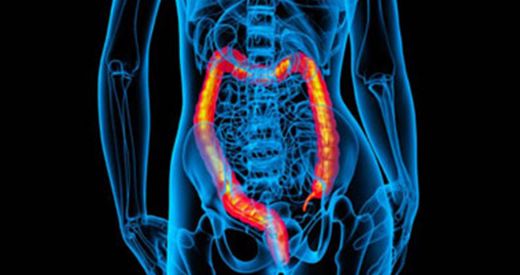

• Endometriozis